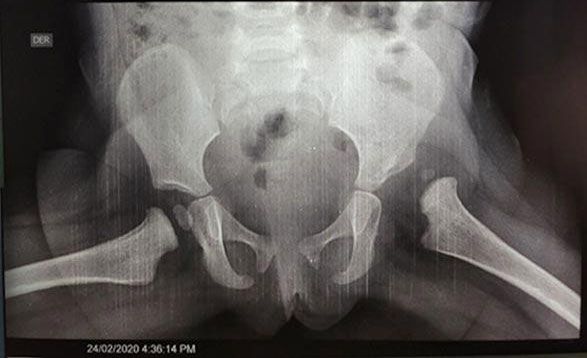

- Luxación Congénita de Cadera: Diagnóstico y corrección de problemas de cadera en recién nacidos.

- Tamiz de cadera

- Displasia de cadera: detección temprana de displasia de cadera por medio de ultrasonido, también conocida como tamiz.